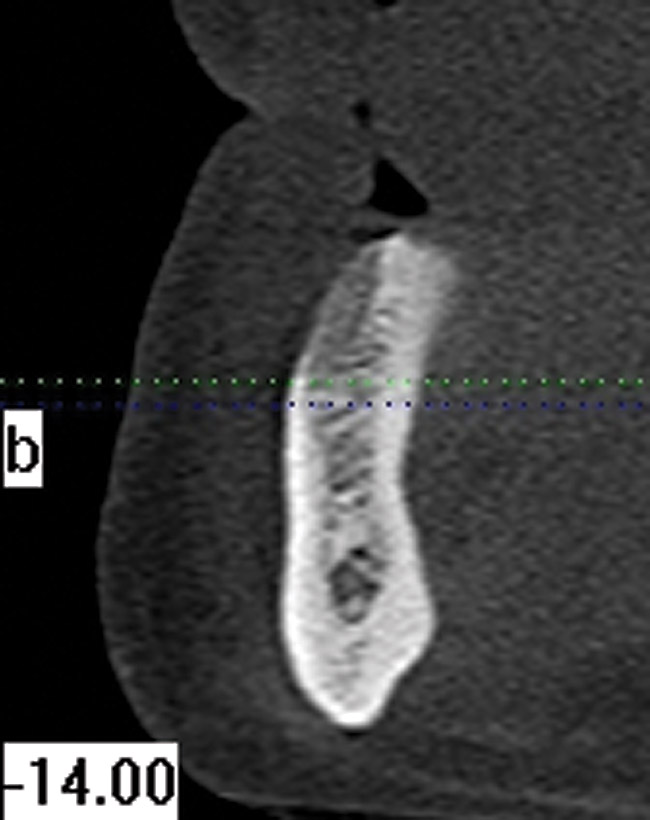

Figure 9  Clinical case of invasive cervical resorption that was deemed nonrestorable and the tooth removed.

Figure 9